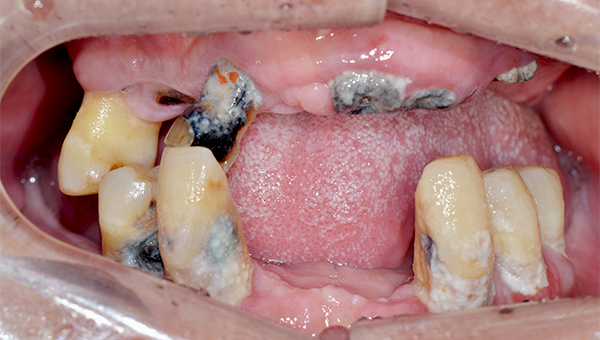

심*복 임플란트 시술 사례

전체 임플란트

2024.12.05

치료 전

2025.05.30

치료 후